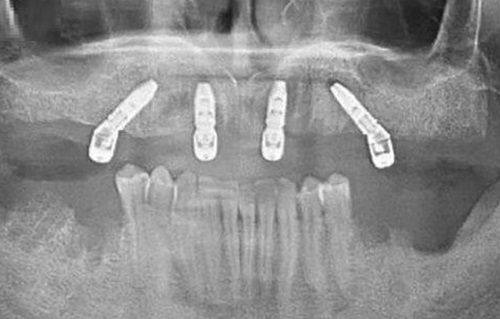

种植牙的修复原理则是“仿生原生式修复”:通过外科手术将人工牙根(种植体)植入缺牙位置的牙槽骨内,待植体与牙槽骨完成骨结合(通常需要3-6个月的愈合时间)后,再安装基台和仿生牙冠。这种修复方式的结构与天然牙几乎一致,人工牙根直接承担咀嚼压力,无需依赖邻牙,能较大程度模拟天然牙的受力逻辑,属于“原生式修复”,对口腔的自然结构破坏极小。

种植牙的适用范围则广泛得多,单颗、多颗、半口甚至全口牙缺失的患者都可选择,但对牙槽骨条件有明确要求:牙槽骨的高度和宽度需不低于5毫米,且全身健康状况良好,没有重度的高血压、糖尿病等基础疾病。如果牙槽骨骨量不足,也可以在医生的建议下精良行植骨手术,补充牙槽骨的高度和宽度后再进行种植,进一步拓宽了适配人群的范围。